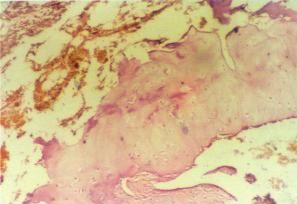

卵泡1、以抑制排卵為主的甾體性激素。雌激素和孕激素口服吸收後血藥濃度增高,通過負反饋作用抑制下丘腦促性腺釋放激素的分泌;此外血中性激素對垂體前葉也有直接抑制作用,可使垂體前葉促性腺激素分泌減少,血中卵泡刺激素(FSH)和黃體生成素(LH)的量均減少,由於FSH分泌受抑制,妨礙卵泡的生長和成熟,沒有成熟的卵泡可供排卵,也取消了排卵前雌激素高峰。由於月經中期的LH峰消失,排卵過程受到抑制。